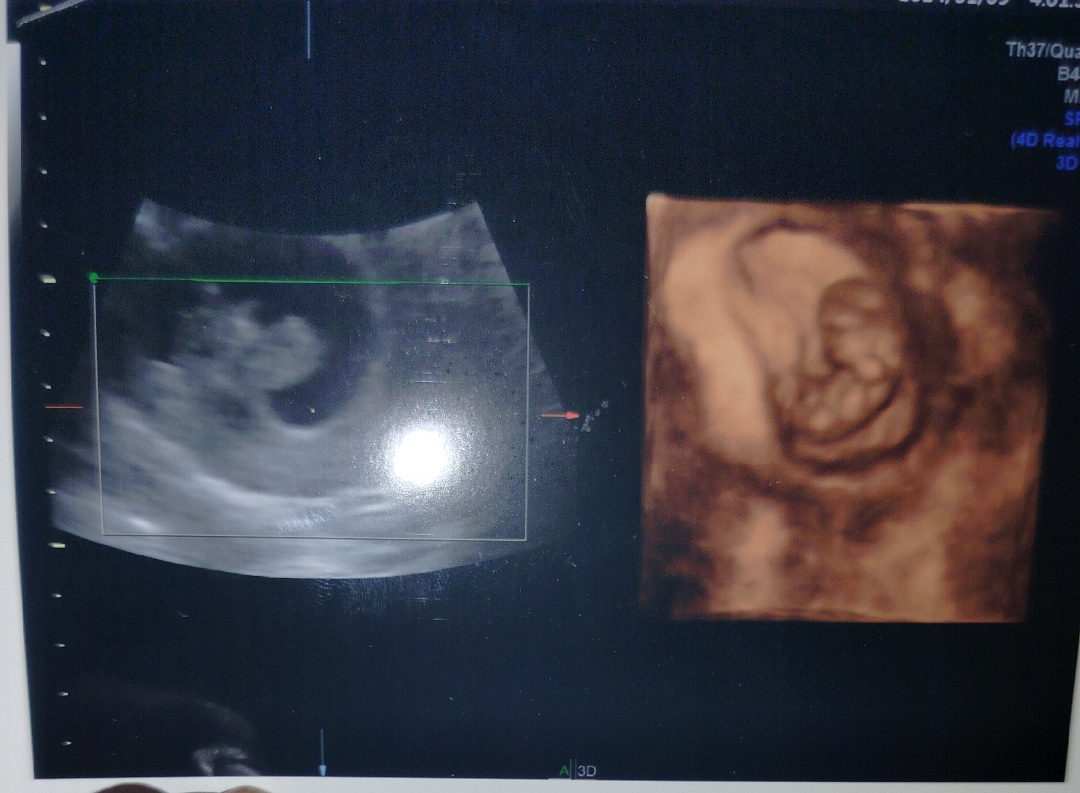

Hai temen2 aku kemarin baru USG, dan dokter bilang aku masuk ke Minggu 10 dan aku melihat janin yang ada di rahim ku sudah mulai kelihatan, tapi aku masih bingung usia 10 Minggu seperti usia 9 Minggu gimana menurut kalian temen2? Apakah sama?

Aku juga kemarin USG udah masuk 10w bunda. Gejala sudah mulai berkurang bahkan tidak separah bulan lalu, saya kaget awal liat USG 6w yang terlihat hanya kantung dan yolk sack, USG ke dua di usia 10w si janin nya gerak gerak Alhamdulillah keadaan nya sehat, semua nya baik. Jadi saya kurang tau bunda apa umur 9-10 itu sama atau tidak.